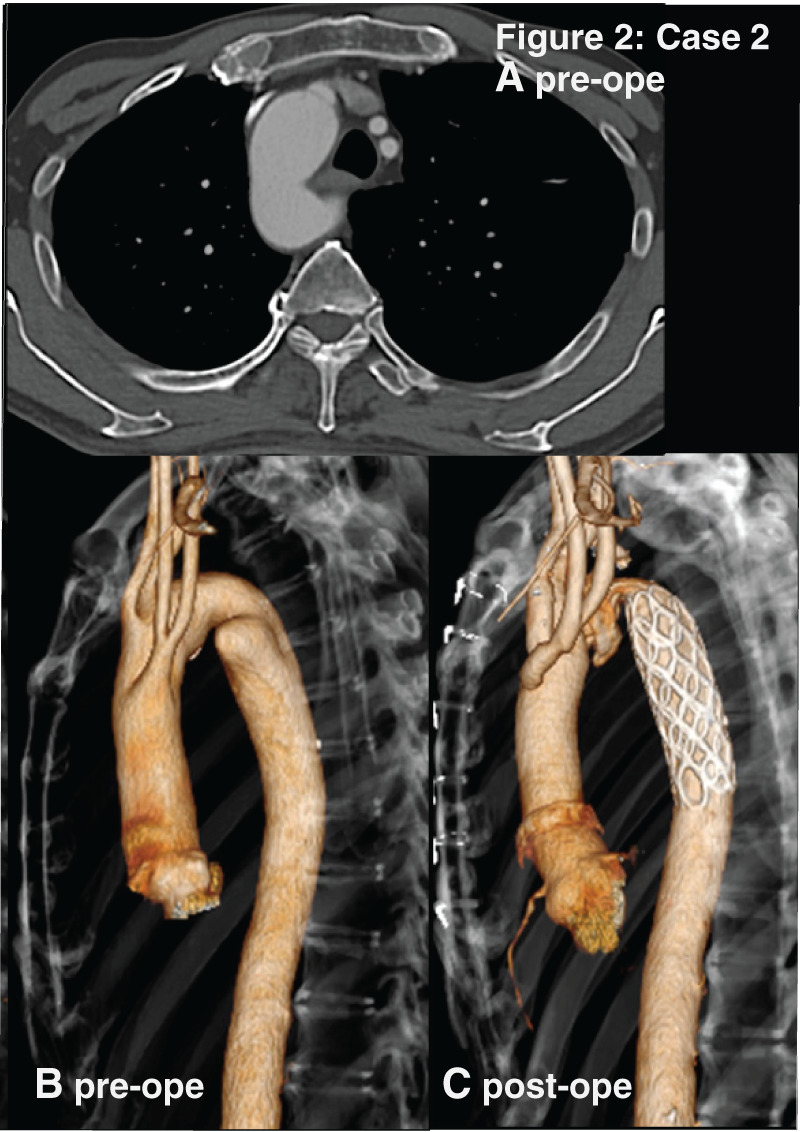

Case presentation: Four patients with right-sided aortic arch underwent different surgeries for Kommerell's diverticulum. The pattern of aortic arch was a mirror-image of the normal left aortic arch in Cases 1 and 2. In Cases 3 and 4, it was right-sided aortic arch with an aberrant left subclavian artery as its last branch. Cases 1 and 3 presented with compression symptoms caused by Kommerell's diverticulum. They underwent open surgery or thoracic endovascular aortic repair through the different approaches. Their postoperative courses were favorable.